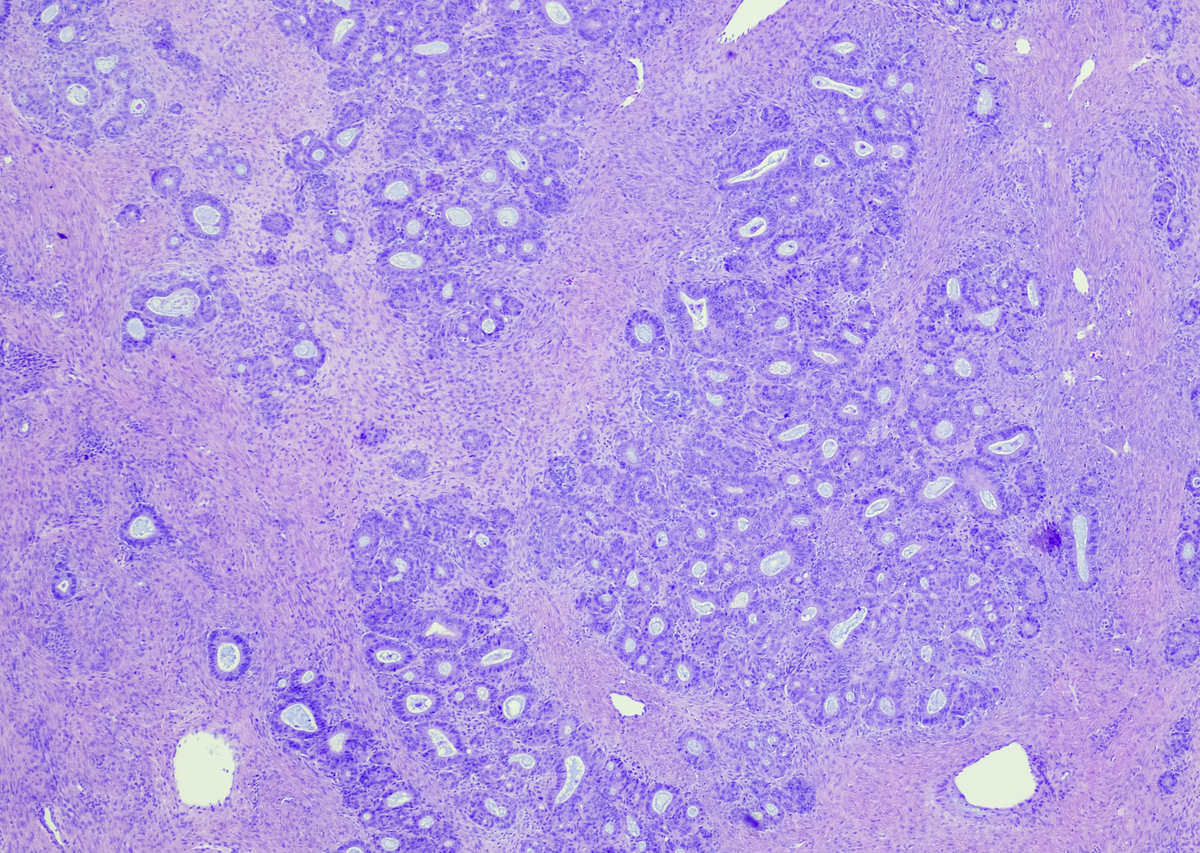

起初,它攻击宫颈的任何细胞,然后扩散到其他细胞。这是全球最恶性和危急的癌症之一。许多生命因这种致命疾病而丧失。